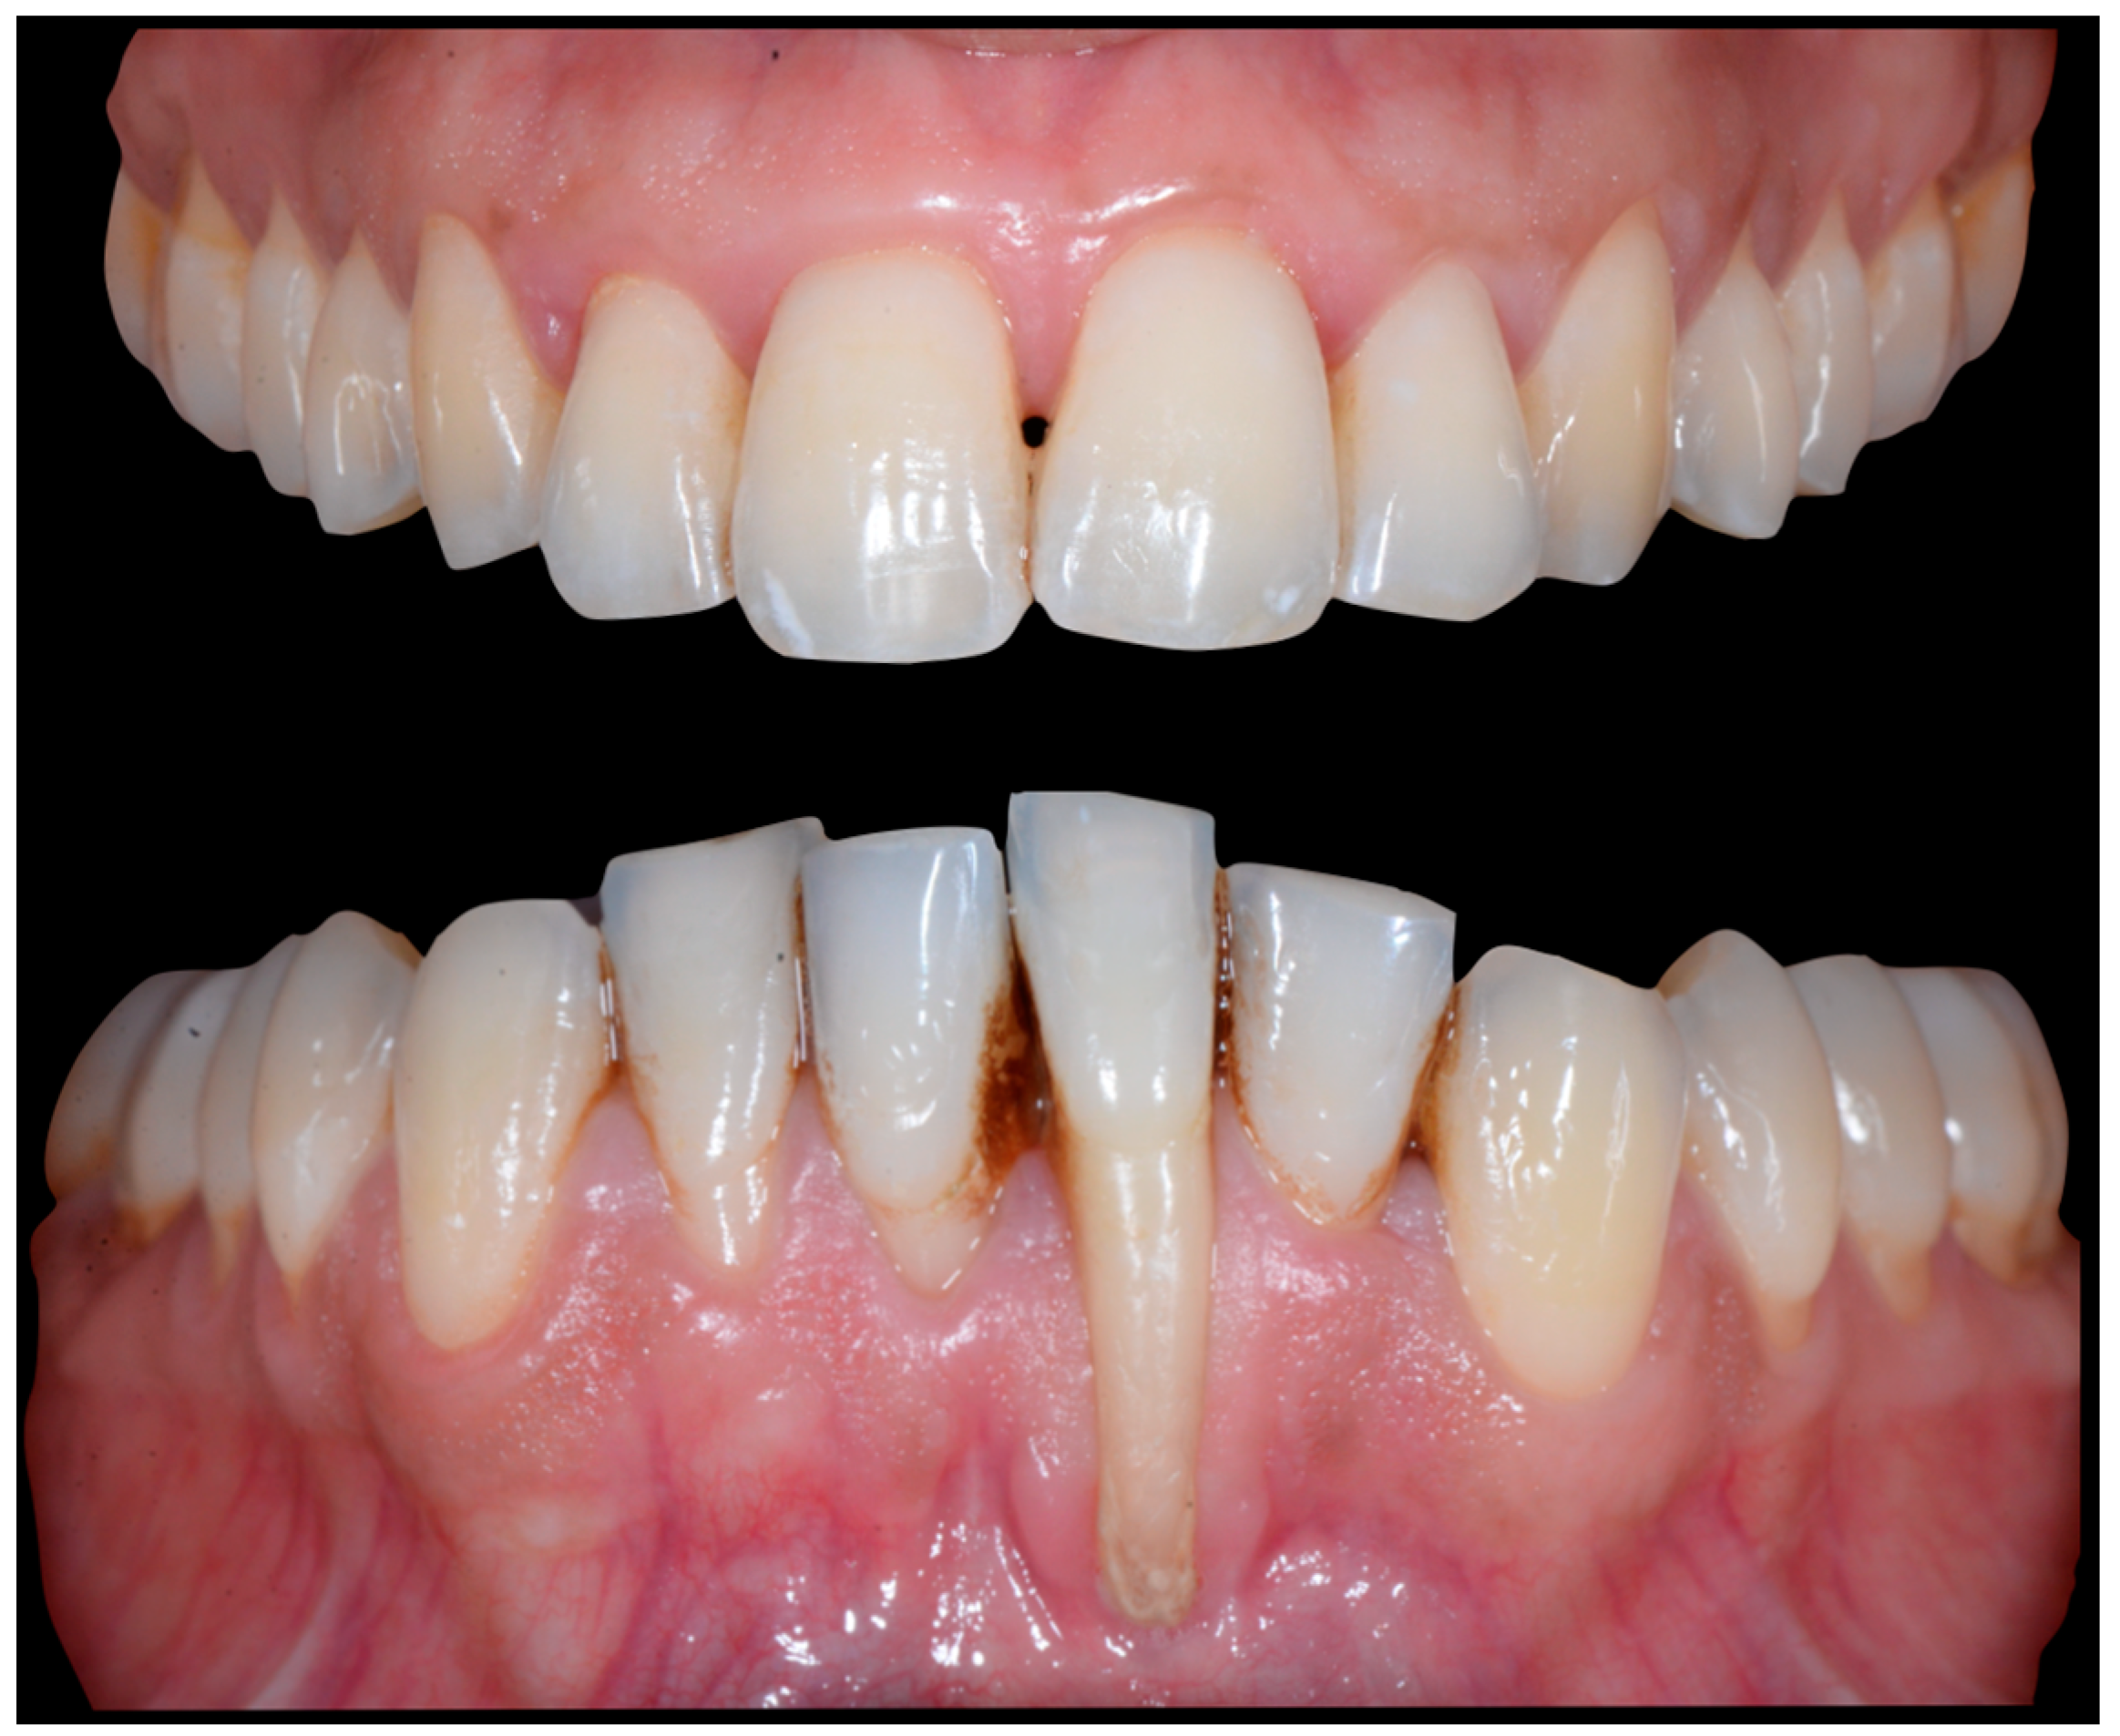

3.3. Severe Wire Syndrome

A 40-year-old patient presented with discomfort in tooth 31, citing past orthodontic treatment. As shown in Figure 11, the patient was in Class I and had poor oral hygiene associated with the presence of calculus in the incisivo-canine region. The root of 31, visible to its apex, was out of the bone and associated with severe gingival recession (Cairo RT2). Teeth 41 and 42 also showed gingival recession (Cairo RT2 and RT1).

Figure 11.

Severe wire syndrome. Frontal and lateral views.

Figure 12 and Figure 13 show a difference in the height of the free edges of the mandibular incisors and the extent of root visibility of 31.

Figure 12.

Severe wire syndrome. Frontal view.

Figure 13.

Severe wire syndrome. Lateral views.

No retainer was present in the maxilla, only a residual mandibular retainer, still bonded to 32 and 42, was visible (Figure 14), as well as incisal crowding and a difference in the visibility of the buccal and root surfaces of 41 compared to the contralaterals. In this extreme clinical situation, a severe and terminal wire syndrome on tooth 41, the “X-effect” type, was observed.